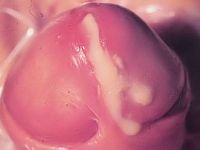

Gonorroe (druiper) Gonorroe (druiper) Intracellulaire diplococcen

gonorroe conjunctivitis gonorroica intracellulaire diplococcen

Foto rechts: CDC Atlanta (Public Domain Images).